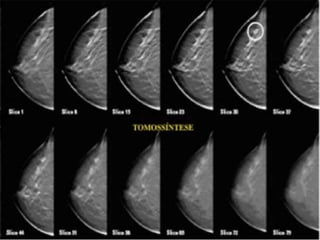

TOMOSSÍNTESE

Além da mamografiaexistem ainda outros meios de diagnóstico de câncer de mama além da mamografia, tais como ressonância magnética, ultrassonografia e tomossíntese.